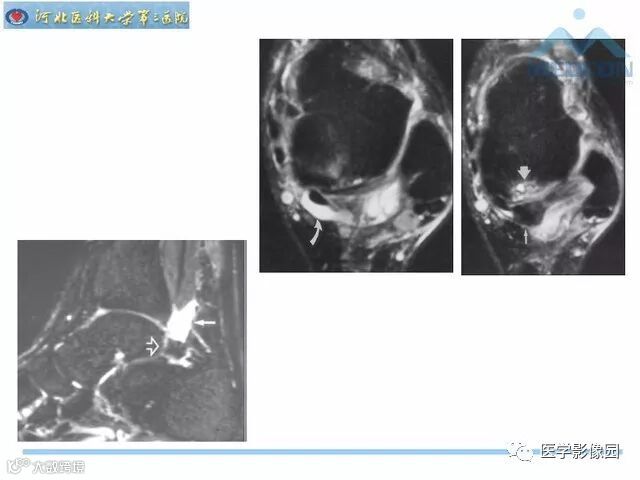

踝关节撞击综合征影像诊断,干货满满,值得收藏!

导读:踝关节撞击综合征影像诊断。干货满满,值得收藏!

踝关节撞击综合征影像诊断。干货满满,值得收藏!